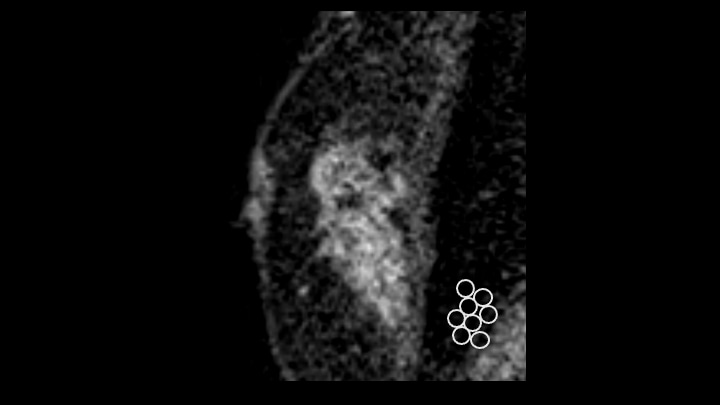

6. 造影後高分解能T1強調画像

内部造影効果 clustered ring enhancementが疑われる。右下:clustered ring enhancementのシェーマ

7. Time intensity curve

Fast-washoutを示す。